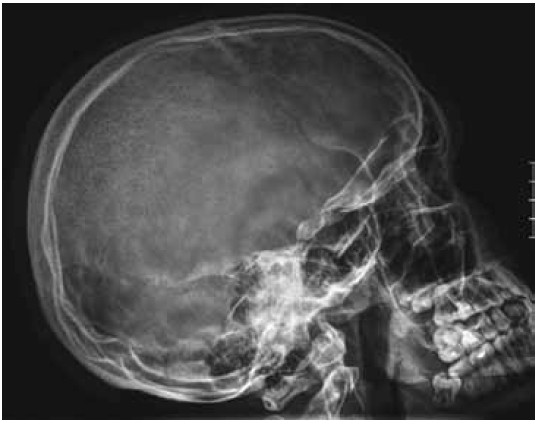

Lateral skull radiograph showed areas of osteolytic changes along the frontal and temporal bones, and osteolytic like area covering the most of the lambdoid sutures (Fig. 4).

Fig. 4. Lateral skull radiograph showed areas of osteolytic changes along the frontal and temporal bones, and osteolytic like area covering the most of the lambdoid sutures